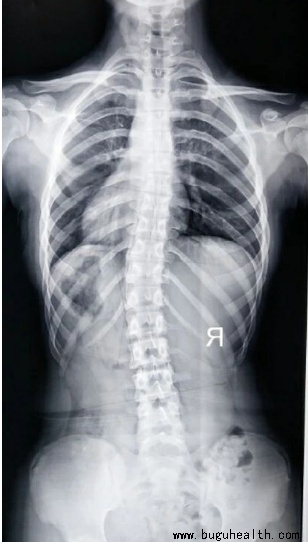

脊柱侧弯是脊柱的非正常弯曲。正常的脊柱在肩部有向后的弯曲,而在腰部有向前的弯曲。典型的脊柱侧弯包括三维的脊柱和肋骨畸形。根据度数的变化,脊柱从侧面弯曲,有时椎骨有轻微旋转,导致髋部或肩部出现不平衡。.....

如今,脊柱侧弯已经成为一个普遍性的问题。据统计,目前我国脊柱侧弯患者超300万,并以每年30万的速度递增,其中超过半数为青少年。脊柱侧弯成为继肥胖症、近视之后,我国儿童青少年健康的第三大“杀手”。要知道,脊柱侧弯不仅影响体型,更重要的是会导致严重的身体健康问题。.....

BuGuRMC布骨康复医疗中心 ,2023-07-07

脊椎侧弯是一种常见的骨骼问题,在站姿下,不管从正面或背面看,正常的脊椎排列应该是身体左右两边对称,并且正常的脊椎排列从上到下是呈一直线的。.....